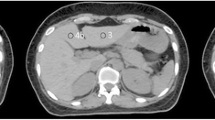

In this study, we analyzed 4D-CT data acquired for the planning of proton beam therapy. Based on these images, the respiratory motion of a high-density lesion and iatrogenic metal (evaluation point) in the liver parenchyma were analyzed as position indicators by a radiation oncologist and a radiation technologist with more than 10 years of experience in RT. For high-density lesions, we targeted areas of calcification and Lipiodol remaining within the vessel in cases of enforcement by hepatic arterial embolization. In surgical patients, we also targeted surgical metal implants (staplers and stents) (Fig. 1).